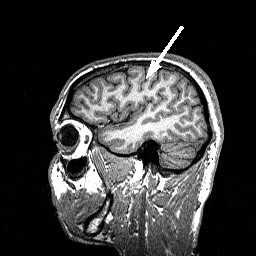

Центральная борозда (sulc.centralis) лучше видна в сагиттальной плоскости. Она расположена по середине между параллельными ей прецентральной и постцентральной бороздами. Существует много вариантов строения и хода борозды. Обычно она имеет значительную протяжённость и идёт в передне-нижнем направлении от межполушарной щели к Сильвиевой щели, которой достигает не всегда. Нижний конец борозды, либо продолжается в основном её направлении, либо загибается назад. Центральная борозда может прерывается по ходу. В поперечной плоскости на верхних срезах борозда имеет наибольшую протяжённость, доходя почти до межполушарной щели. Чем ниже срез, тем короче на нём центральная борозда. На уровне боковых желудочков она едва прослеживается . Центральная борозда разграничивает лобную и теменную доли .

МРТ головного мозга. Латеральный сагиттальный срез. Центральная борозда (стрелка).